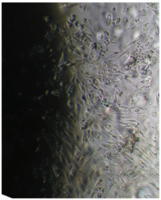

Культуру дермальных фибробластов получали из кожно-мышечной ткани, а культуру мезенхимальных стромальных клеток – из фрагментов крыши черепа абортусов сроком 6-10 недель методом первичных эксплантатов (рис. 1, 2).

Вид монослоя и структура клеток не отличались от обычных в течение всех четырех суток наблюдения (рис. 32).

Это свидетельствует об умеренной стимуляции пролиферации фибробластов в культуре под влиянием недеминерализованной спонгиозы (таб. 9.).

2 серия экспериментов. В культуральные чашки помещали образец исследуемого материала (кусочек недеминерализованной спонгиозы серии «Лиопласт»® объемом 125 куб. см), после чего высевали фибробласты в концентрации 20000 клеток/см².

Наблюдение через сутки показало, что фибробласты хорошо пристают к дну культуральной чашки, образуют равномерный монослой с плотностью 311 клеток/мм².

Фибробласты были распластаны по дну чашки, имели обычную для этих клеток удлиненную форму, 2-4 отростка, клеточная и ядерная оболочки четко контурировали.

Цитоплазма представлялась гомогенной (рис. 33). Большинство клеток имели одно центрально расположенное ядро правильной округлой формы с 1 или 2 ядрышками.